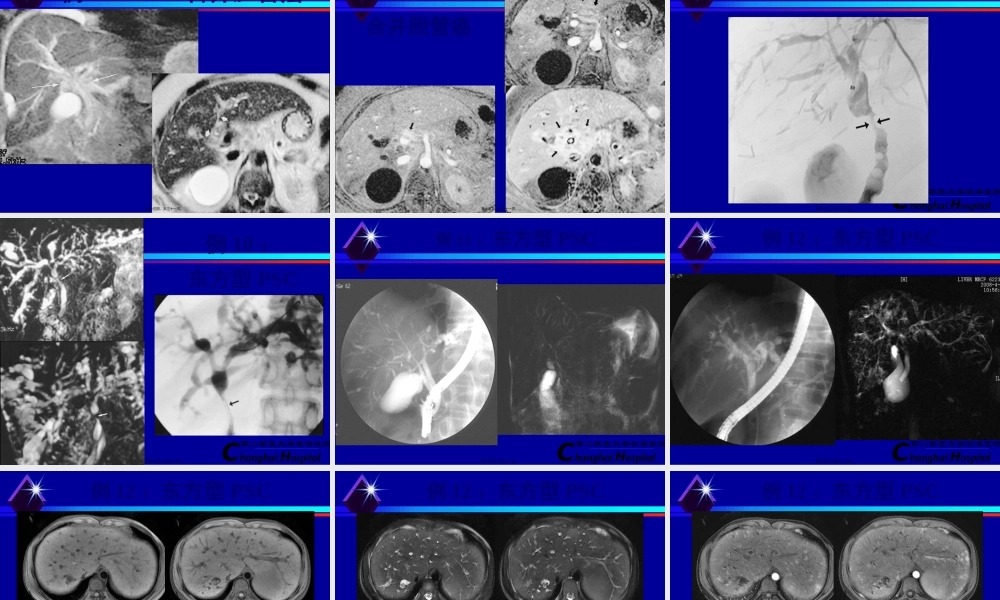

ChanghaiHospital第二军医大学长海医院原发性硬化性胆管炎primarysclerosingcholangitis(PSC)第一页,共三十一页。ChanghaiHospital第二军医大学长海医院概述原发性硬化性胆管炎是一种原因不明的慢性淤胆性肝病,以进行性肝内外胆管慢性炎症、破坏和纤维化为特征,逐渐出现胆管不规那么狭窄、减少直至小胆管消失。虽然进展缓慢,但它最终必将导致大局部患者出现肝硬化、门脉高压、肝衰竭或恶性肿瘤而死亡。第二页,共三十一页。ChanghaiHospital第二军医大学长海医院临床病症与诊断黄疸、体重减轻、搔痒前三位主要病症典型实验室表现为胆汁淤积性肝酶异常的特点:即碱性磷酸酶AKP水平通常高于正常上限的5倍,而转氨酶ALT水平仅轻微升高ERCP胆道造影术是诊断硬化性胆管炎的金标准第三页,共三十一页。ChanghaiHospital第二军医大学长海医院影像表现ERCP或MRCP胆道造影可见:肝内外胆管多发性狭窄与扩张、弥漫性狭窄中夹有正常或扩张的较短胆管形成“串珠状〞改变第四页,共三十一页。ChanghaiHospital第二军医大学长海医院例1:PSC右肝管明显第五页,共三十一页。ChanghaiHospital第二军医大学长海医院例2:PSC肝胆总管明显第六页,共三十一页。ChanghaiHospital第二军医大学长海医院例3:MRCP肝总管假阳性第七页,共三十一页。ChanghaiHospital第二军医大学长海医院例4:早期PSC第八页,共三十一页。ChanghaiHospital第二军医大学长海医院例5:PSC合并胆囊管低汇第九页,共三十一页。ChanghaiHospital第二军医大学长海医院例6:PSC胆肠吻合第十页,共三十一页。ChanghaiHospital第二军医大学长海医院例7:PTC限制第十一页,共三十一页。ChanghaiHospital第二军医大学长海医院例8:PSC环状狭窄征第十二页,共三十一页。ChanghaiHospital第二军医大学长海医院例8:PSC“憩室〞征第十三页,共三十一页。ChanghaiHospital第二军医大学长海医院例9:PSC合并胆管癌第十四页,共三十一页。ChanghaiHospital第二军医大学长海医院例9:PSC合并胆管癌第十五页,共三十一页。ChanghaiHospital第二军医大学长海医院例9:PSC合并胆管癌第十六页,共三十一页。ChanghaiHospital第二军医大学长海医院例10:东方型PSC第十七页,共三十一页。ChanghaiHospital第二军医大学长海医院例11:东方型PSC第十八页,共三十一页。ChanghaiHospital第二军医大学长海医院例12:东方型PSC第十九页,共三十一页。ChanghaiHospital第二军医大学长海医院例12:东方型PSC第...